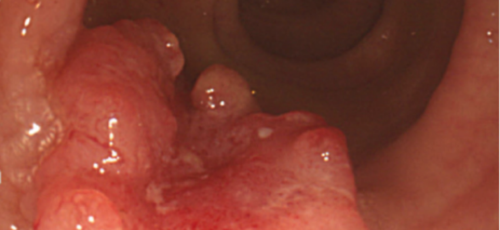

대장내시경

대장암을 초기에 발견해 내려면 대장내시경은 필수인데요 적어도 2년에 한 번 대장내시경을 받아 이상이 없나 확인해 봐야 합니다.CT촬영으로 혹이 보이거나 하는 경우가 있는데요, 사실 초기에 CT로 혹을 잡아내기는 매우 힘들다고 해요. 가장 정확한 건 의사가 눈으로 볼 수 있는 대장내시경이니 건강검진시 꼭 받으시기 바랍니다.

대장암 초기증상은 만성복통과 소화불량, 식욕저하, 변비, 설사 등의 다양한 형태로 나타날 수 있습니다. 하지만 초기에는 이렇다할 증상이 보이지 않아 건강검진을 하면서 우연히 발견되기도 합니다. 따라서 대장암을 조기에 발견하고 적기에 치료하기 위해서는 대장내시경 검사를 정기적으로 받는 방법뿐인데요 45세부터는 5년에 한 번씩 대장내시경 검사를 받도록 권장되고있는데, 만약 가족 중 대장암환자가 있거나 유전적 요인이 있는 경우에는 40세부터 정기적으로 검사받는것이 좋습니다.

특이 증상이 없더라도 국가에서 권장하고있는 건강검진 시기에 맞게 대장내시경을 하는 것이 좋습니다. 또한 이러한 증세가 나타난다면 빠른 시일 내에 진료를 통한 내시경 검사를 진행하여 정확한 진단과 그에 맞는 치료가 진행되어야 합니다. 꼭 대장암 초기증상이 아니더라도 대장질환이나 위장질환으로 인해 상황이 악화되어 나타날 수 있기때문에 그냥 넘기지않고 꼭 내원하여 적절한 치료를 받는것이 좋습니다.